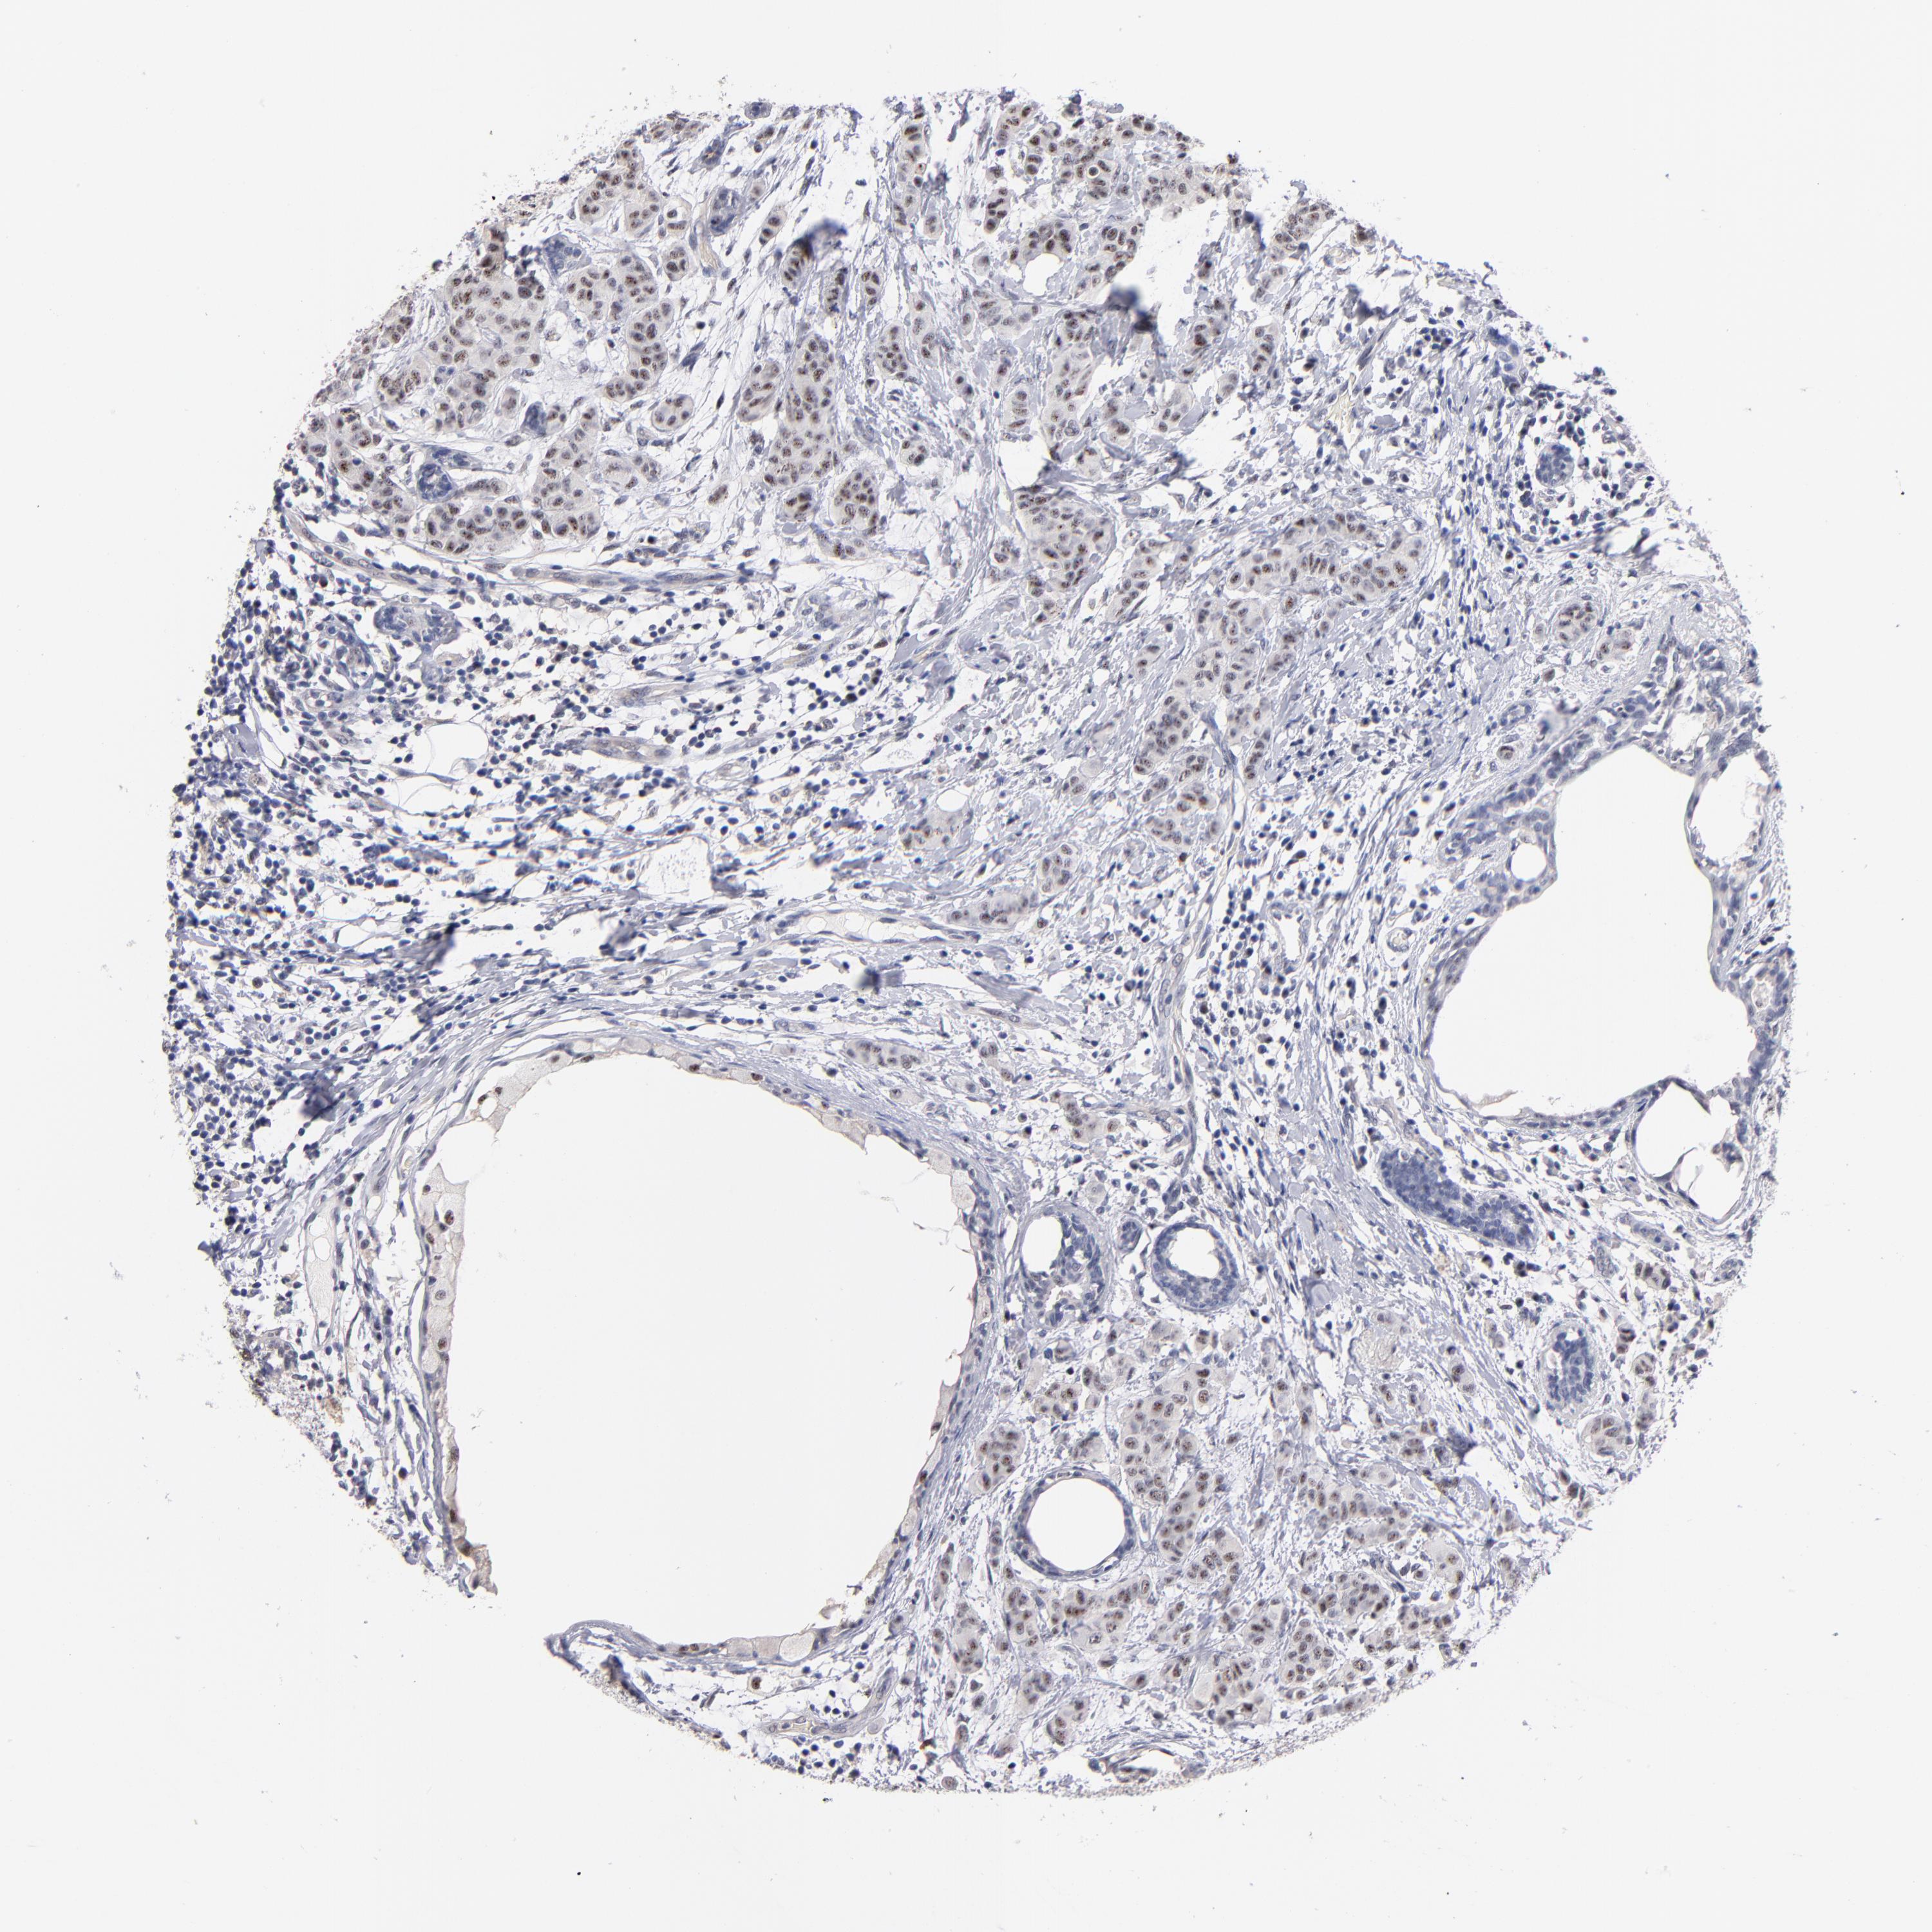

BRCA TCGA BRCA VALIDATION PROTEIN EXPRESSION